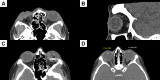

Ocular trauma may either be closed globe or open globe. Open globe injuries are full-thickness defects of the eyewall and are often differentiated by the mechanisms of injury from which they are caused: sharp or blunt trauma. They are ocular emergencies and can lead to substantial visual morbidity. Without timely intervention, damage is irreversible and leads to permanent vision loss. The goals of evaluation are to identify the mechanism of injury, characterize the extent of injury, and gather relevant history. If an open globe is suspected, ophthalmologic consultation should be requested. Once an open globe is diagnosed, preparations for surgery should be made immediately and steps should be taken to avoid further injury. Intraocular infection risk is relatively high, requiring immediate empiric systemic antibiotics. Emergent surgical exploration and primary closure is indicated whenever possible. After initial closure, secondary surgery and revision may be needed to improve vision outcomes, followed by extensive follow-up. In this review, best practices for evaluation and management are reviewed, with particular focus on the surgical approach and techniques.